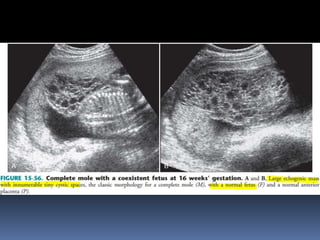

This document contains an image gallery from Dr. Mohit Goel showing various uterine anomalies and ovarian cysts. It includes images of an arcuate and unicornuate uterus, endometritis, a twisted ovarian pedicle, dermoid cysts of varying sizes and echogenicity containing hair, fat, and calcifications, and a combination dermoid cyst showing both mesh and plug structures. The gallery provides ultrasound images of different gynecological conditions for medical education and reference.